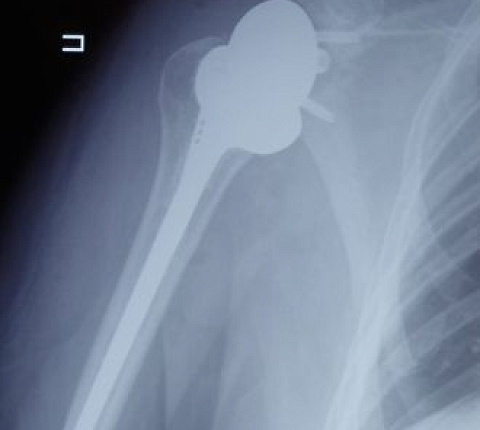

Чтобы восстановить функцию плечевого сустава, врачи травматолого-ортопедического отделения ФМБЦ им. А.И. Бурназяна ФМБА России впервые выполнили реверсивное эндопротезирование плеча. В ходе операции хирурги удалили поражённую головку плечевой кости, на место которой поместили реверсивный эндопротез – плечевой компонент протеза вогнутый, а со стороны лопатки выполнен в форме сферы. Такой тип протеза позволяет восстановить функцию сустава при дефиците мышц вращательной манжеты плеча и показывает лучшие результаты, чем другие эндопротезы.